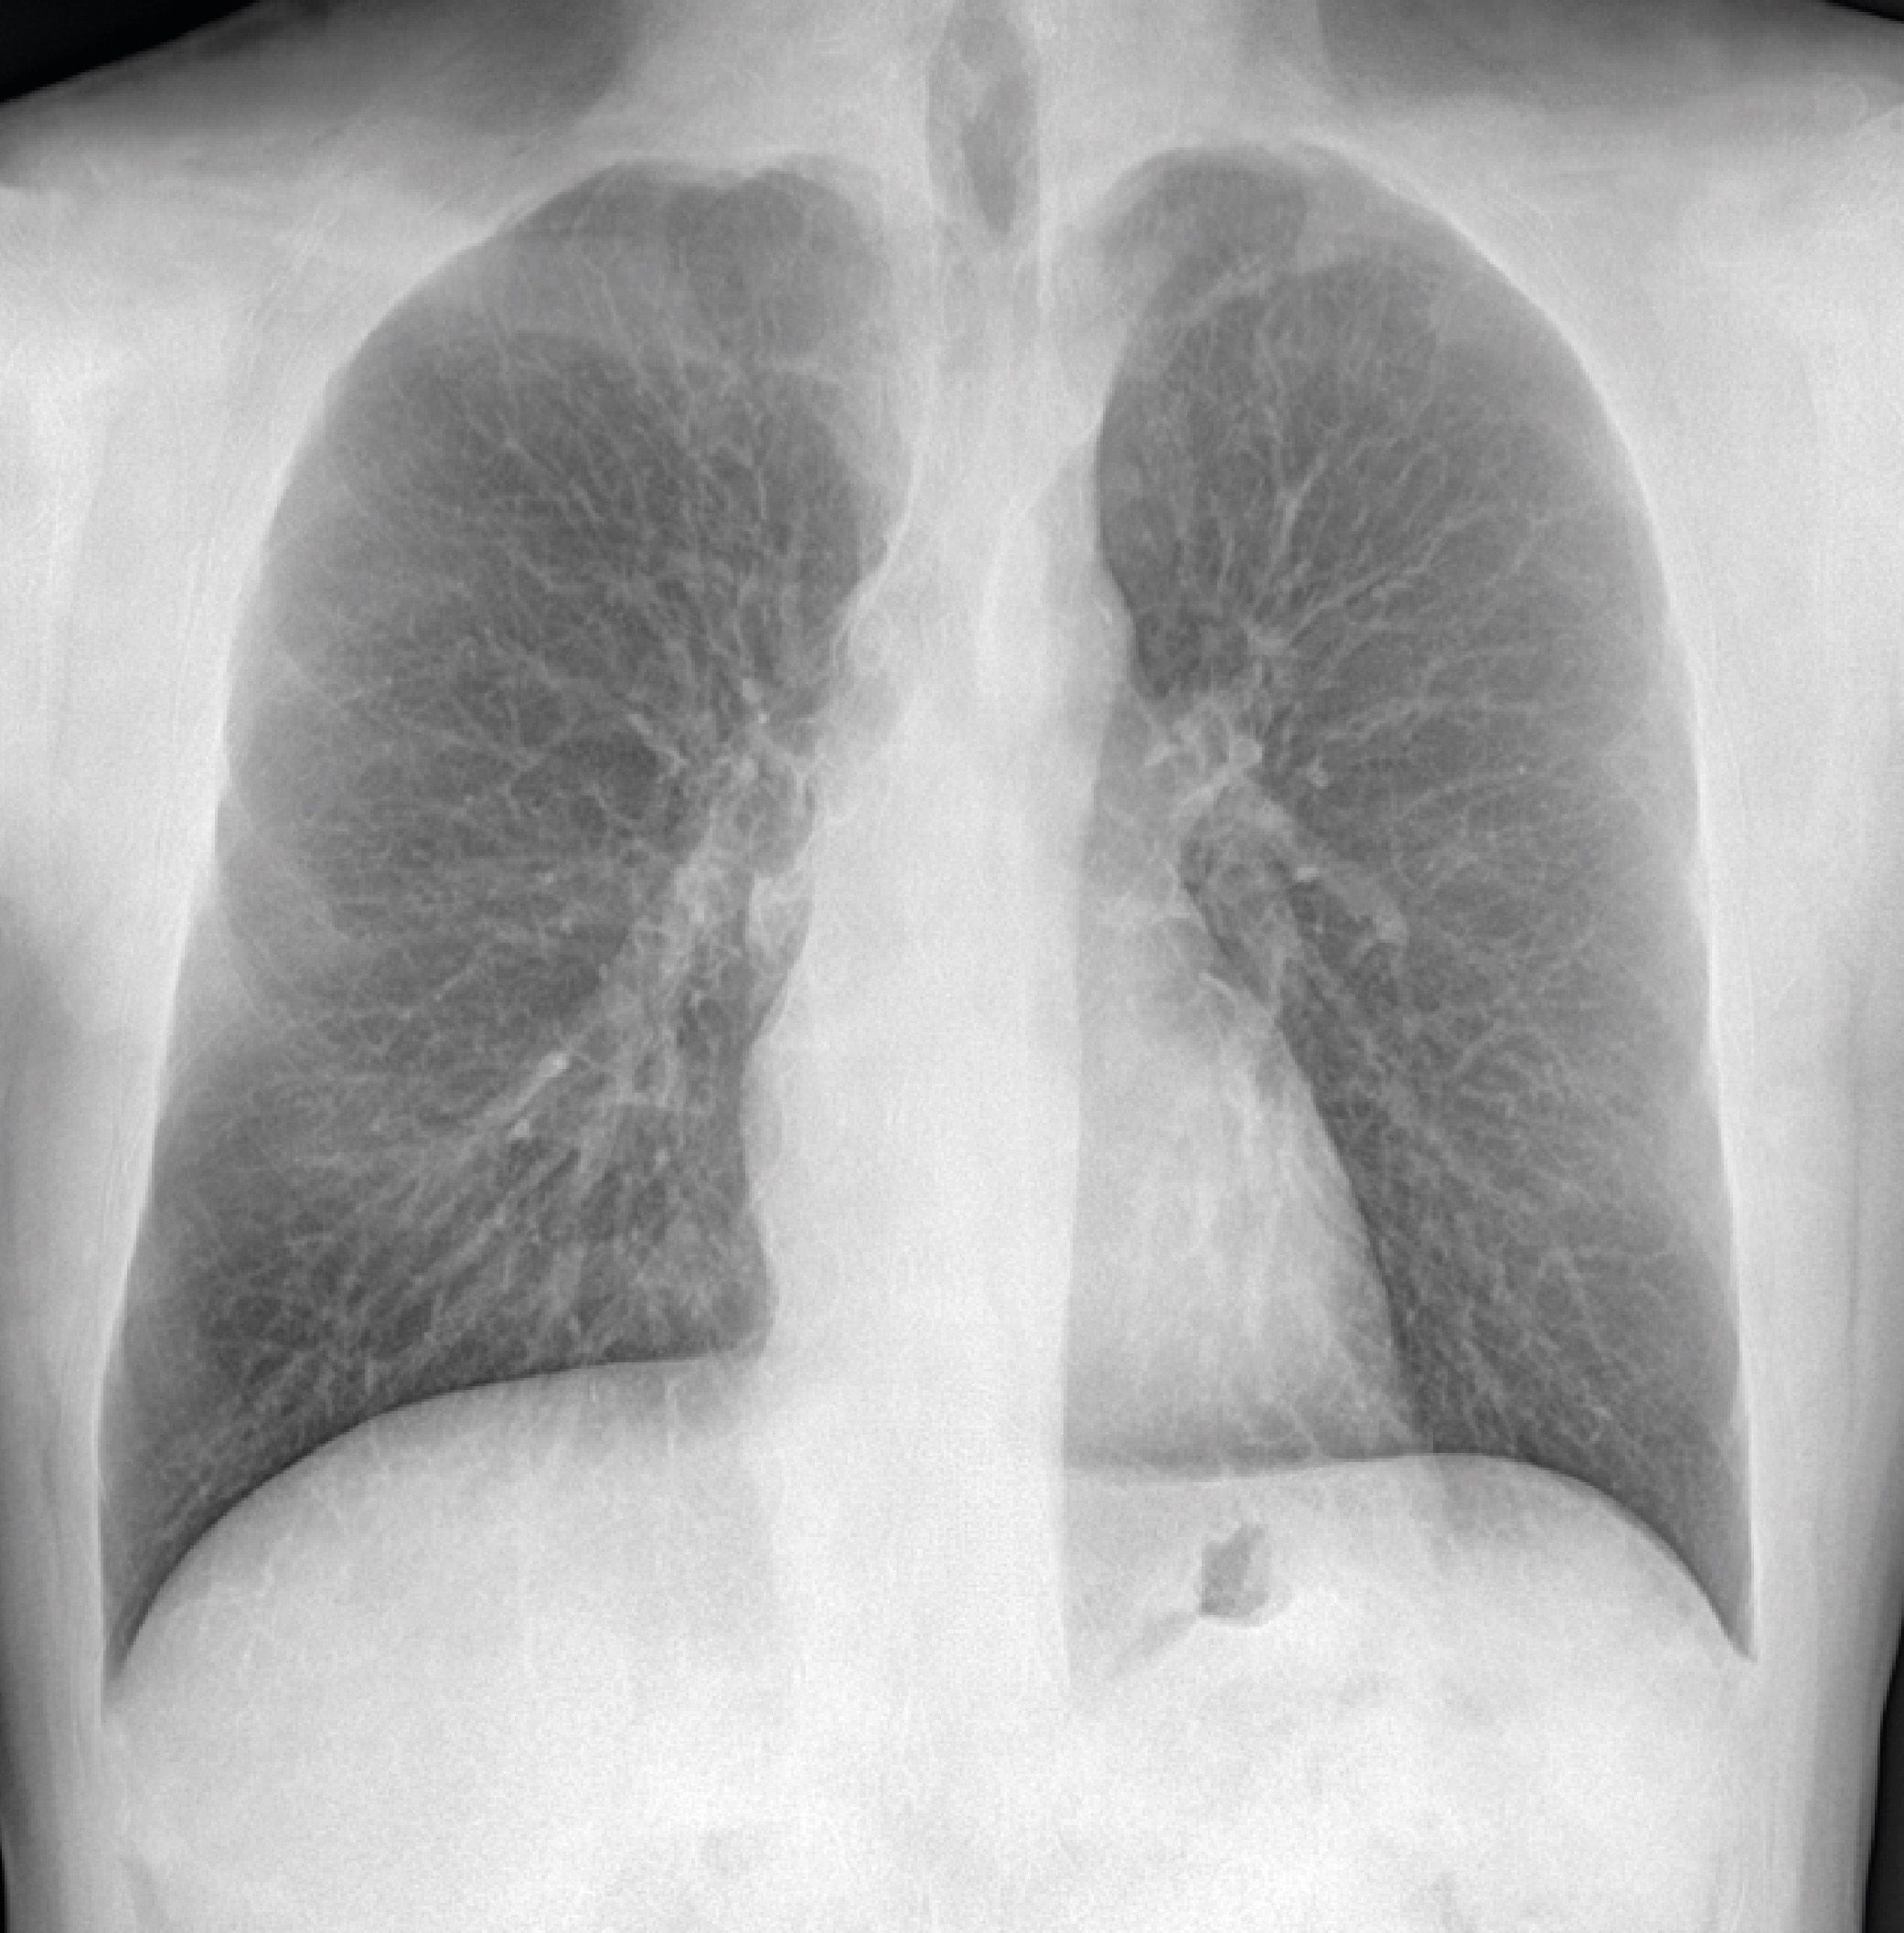

Bone Suppression è un algoritmo di post-processing che rimuove la componente ossea dall’immagine di una radiografia standard del torace favorendo la visibilità dei tessuti molli e di eventuali lesioni.

Interpretare una radiografia del torace può rivelarsi complicato: le strutture ossee a elevato contrasto presenti (coste e clavicole) possono oscurare del tutto o in parte le lesioni polmonari, ed essere perciò alla base di errori se non addirittura di mancate diagnosi.

Bone Suppression si propone di fornire un’immagine RX con migliore visibilità del campo polmonare mediante la riduzione del rumore causato dalle strutture ossee.

Grazie all'algoritmo di Bone Suppression è possibile, a partire da un'immagine radiografica standard del torace ottenuta con una singola esposizione e ricorrendo all'implementazione di un algoritmo basato sull'Al, rimuovere automaticamente le strutture ossee e ottenere un output di qualità elevata che faciliti la visibilità dei tessuti molli senza necessità di esporre il Paziente a dosi addizionali di radiazione.

Senza comportare appesantimenti o rallentamenti, senza richiedere ulteriori acquisizioni né comportare incrementi di dose di radiazione somministrata al Paziente, a partire dall’immagine RAW l’algoritmo di Bone Suppression genera un’immagine addizionale - anch’essa RAW - con la componente ossea rimossa. A quest’immagine aggiuntiva (e non sostitutiva della proiezione standard) potrà poi essere applicato il normale post-processing manuale eventualmente ritenuto necessario ai fini di visualizzazione e refertazione.